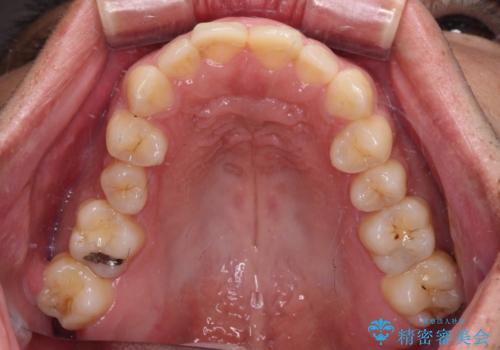

- 競技用自転車を運転中に転倒して前歯を強くぶつけ、欠けてしまったとのことで来院された患者様です。

近医にて欠けて部分を樹脂で修復してもらったものの、舌での感触が悪く、しみる感覚があるため、オールセラミッククラウンによる補綴治療を希望されていました。

仮歯に置き換え、しみる感覚が改善されてことを確認された後に、オールセラミッククラウンにて補綴治療を行うこととしました。